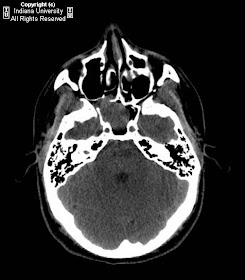

CT shows a soft tissue mass extending from pterygopalatine fissure into sphenoid sinus with some erosion and expansion of adjacent bony structures. Angiography shows a major hyper vascular tumor supplied by sphenopalatine branch of right internal maxillary artery, without ascending pharyngeal artery supply. Minimal tumor blood supply from sphenopalatine branch of left internal maxillary artery. Super selective embolization of left and right sphenopalatine arteries was performed using Echelon-14 micro catheter and RVA particles (150-250 microns).

Most suggestive finding is a homogenous, nasopharyngeal soft tissue mass causing expansion of the nasal cavity, sometimes with septal deviation, and extending into the pterygopalatine fossa and sphenoid sinus.

Often see anterior bowing of the posterior wall of the ipsilateral maxillary sinus, but rarely with breakthrough into the antrum. Conversely, the tumor often extends superiorly with erosion into the sphenoid sinus, and possibly with extension into the cavernous sinus.